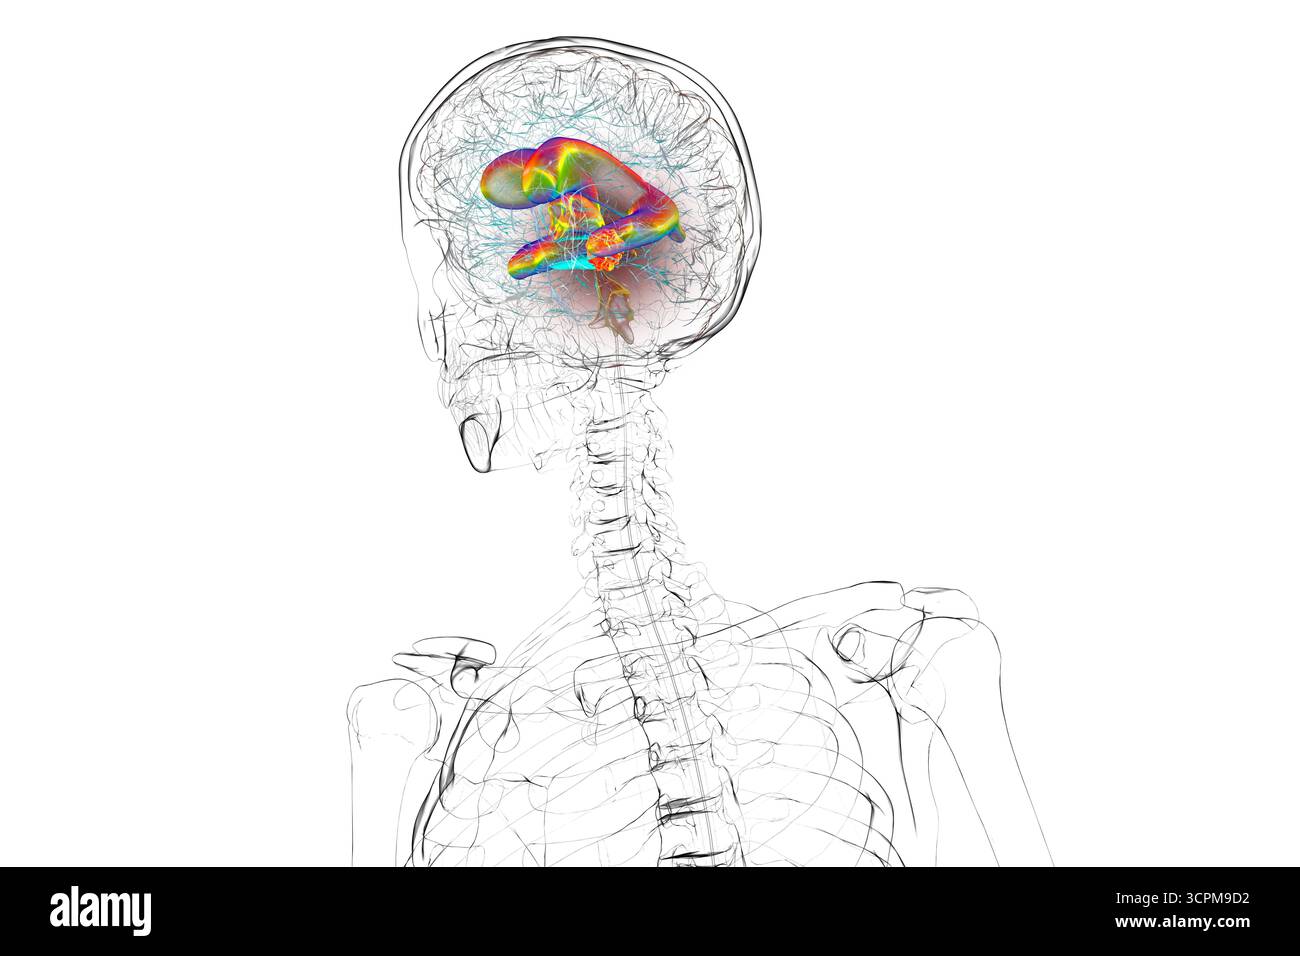

RF3CN8WHP–Illustration des vergrößerten lateralen und dritten Ventrikels des Gehirns (Hydrozephalus), hervorgerufen durch einen Hirntumor, der den Aquädukt des Gehirns komprimiert.

RF3CPM9D2–Darstellung der vergrößerten lateralen und dritten Ventrikel des Gehirns (Hydrozephalus), hervorgerufen durch einen Hirntumor, der den Aquädukt des Gehirns komprimiert.